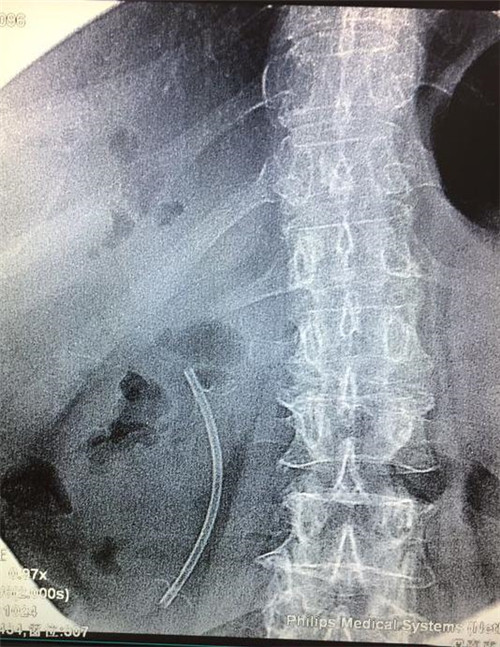

经过多个科室的配合,在介入科X线机下,曹鹏医生于十二指肠镜下顺利将导丝插入患者胆管内,注入二氧化碳气体造影,X线下见患者肝内外胆管扩张,胆管末端明显有占位性病变,患者胆管末端因肿瘤压迫,非常狭窄,经过多级扩张后,顺利为患者置入胆道支架。手术非常顺利,患者生命体征平稳,大家都松了口气。

2天后,曹鹏医生对其进行术后随访,各项化验指标明显好转,患者精神良好,全身皮肤粘膜黄染较前缓解,主诉无明显腹痛,食纳可。